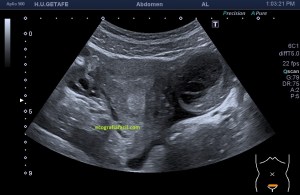

Bien, hemos visto una lesión que es un quiste hidatídico calcificado, pero te preguntarás, si nunca viste uno, ¿cómo es uno cuando tiene «hijas»?, es decir, cuando está activo…Mira este corte transversal de un hígado:

La LOE es de aspecto redondeado, heterogéneo, con multitud de pequeñas imágenes anecoicas e hipoecogénicas, de diferentes tamaños. Esta lesión fue estudiada también mediante otra técnica de imagen, la RMN donde se observa una imagen hiperdensa, con una amalgama de lesiones bordeando a periferia de la misma, de distintos tamaños como se objetiva en la imagen del mismo paciente, de la ecografía inmediatamente superior (Imagen 7). La lesión es activa, por tanto debió de ser tratada, la patología es potencialmente mortal en caso de que el quiste se rompiese.